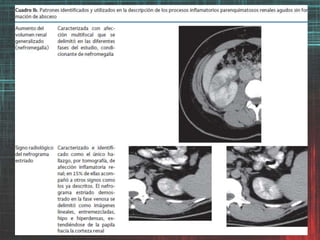

Hallazgos por imagende los procesos inflamatorios del trayecto urinario. Valor clínico de la graduación de la Pielonefritis aguda (PA) basada en hallazgos de TC -afección parenquimatosa- como factor predictivo de severidad y evolución de la PA. Grado 1 Sin afección demostrable por TC Grado 2 Afección demostrable por TC menor al 25% Grado 3 Afección demostrable por TC mayor del 25% pero menor del 50% Grado 4 Afección demostrable por TC por arriba del 50% Paick SH, Choo GY, Baek M, Bae SR, Kim HG, Lho YS et al. Clinical value of acute pyelonephritis grade based on computed tomography in predicting severity and course of acute pyelonephritis. J Comput Assist Tomogr 2013;37: 440-442